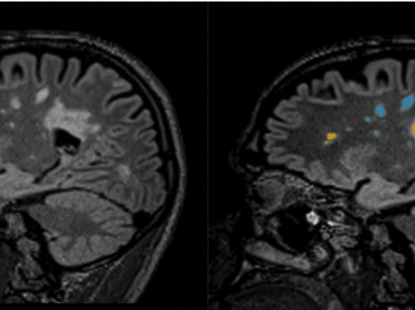

Multiple Sclerosis Awareness Month takes place every March, and this year is no exception. The goal of this awareness campaign is to help the public ...

Read More